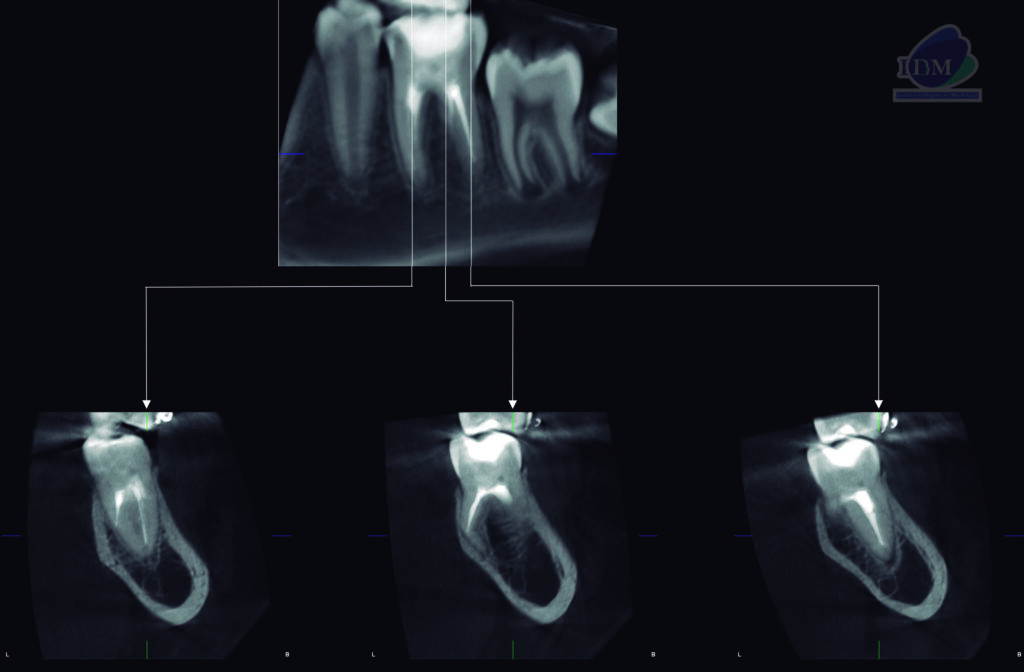

A la evaluación de la tomografía volumétrica (CBCT) en los cortes axiales (Figura 2) y transaxiales (Figura 3), se aprecia marcada dilaceración de raiz supernumeraria en lingual de la pieza 36 que ocasiona el adelgazamiento de la tablo osea lingual. signos tomográficos compatible con radix entomolaris.

En las reconstrucciones 3D se representa de manera didáctica raiz supernumeraria (Radix Entomolaris). (Figura 4).

RECONSTRUCCIÓN 3D

- Radix Entomolaris.